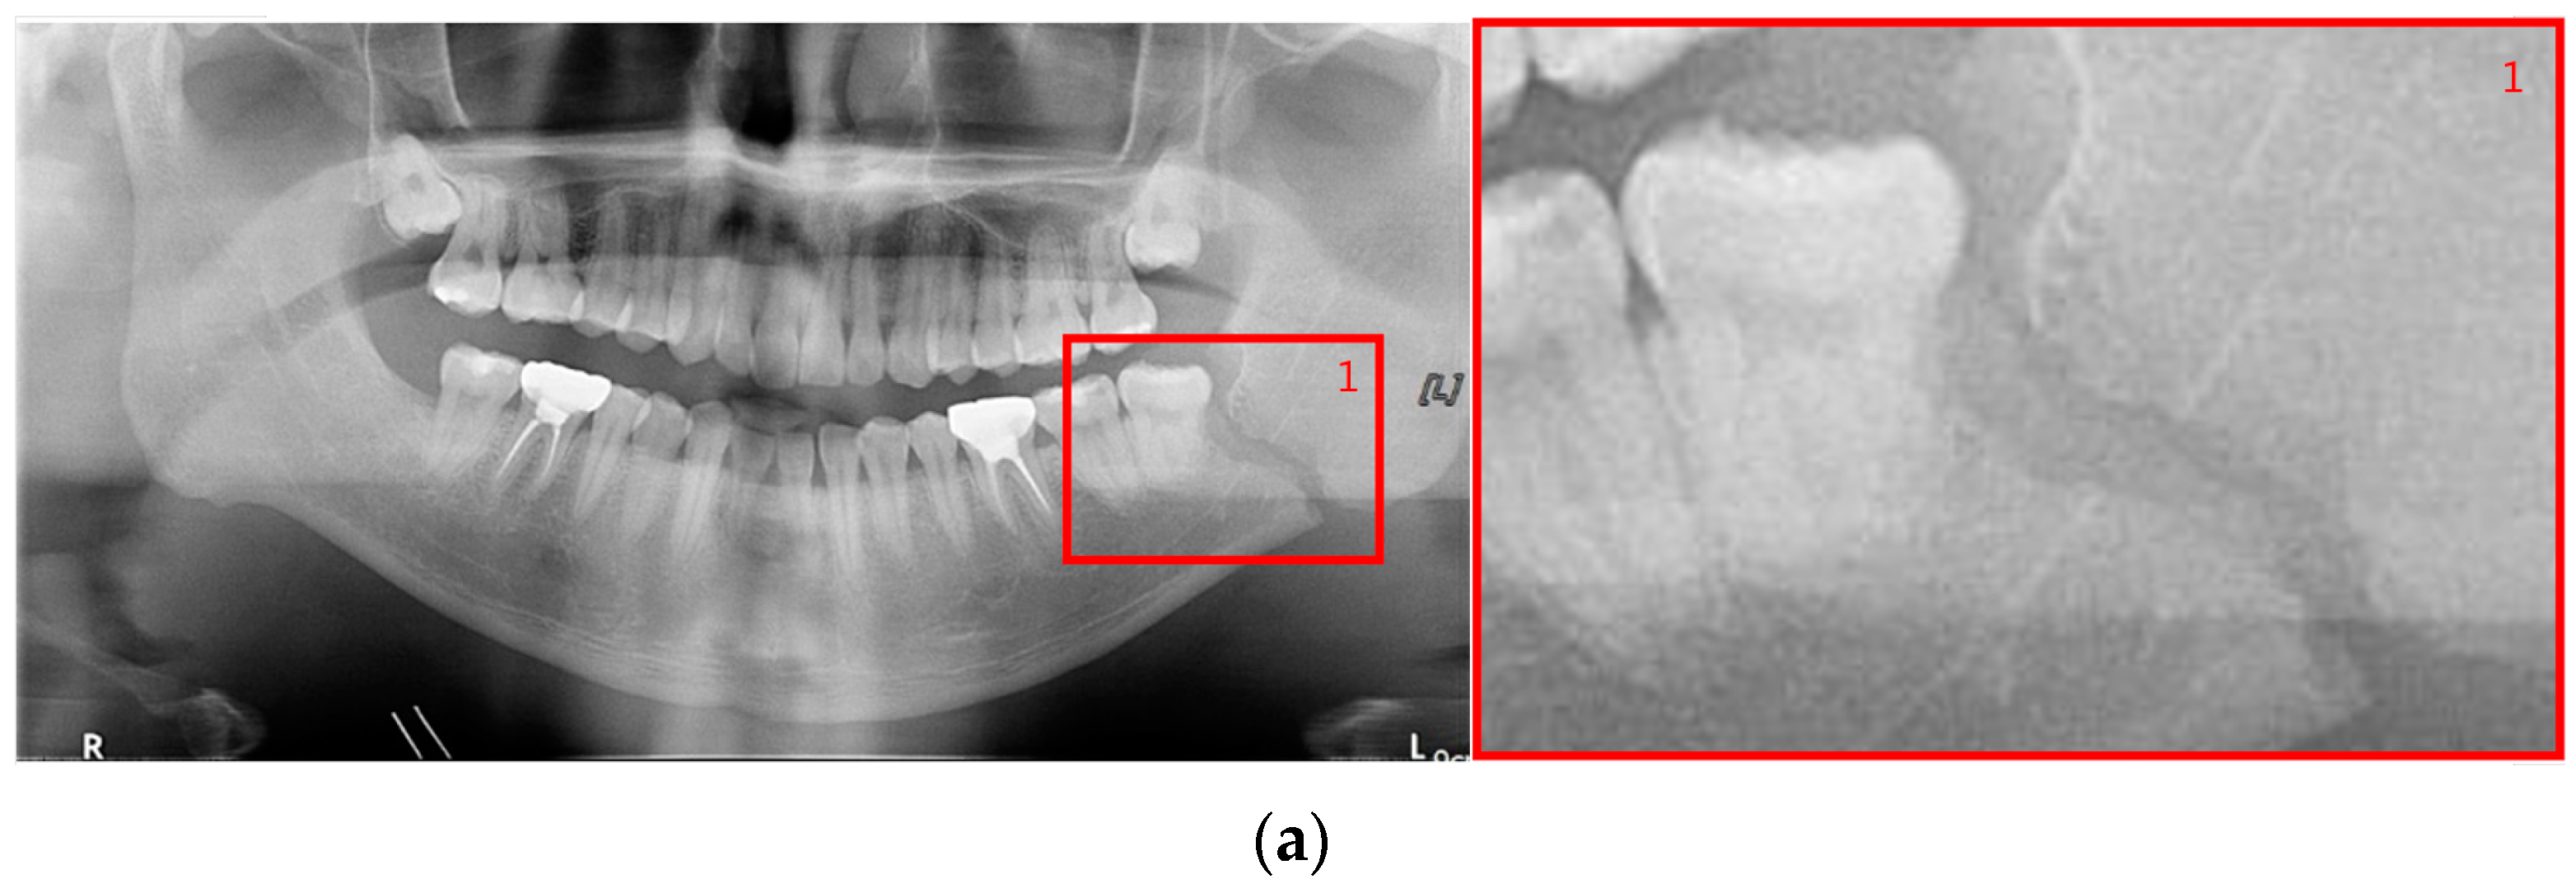

The shape of fractures in the panoramic radiographic image generally shows an oblique fracture with a gap and a shear fracture with a step in red boxes one and two (Figure 2). However, in the condyle region, the fracture shape differs from the general fracture shape, and the bones in the condyle region seem to overlap (dislocation) in red boxes 3 and 4 [7]. Owing to the similarity between the phenomenon that looks like a fracture due to the difference in shading on the panoramic radiographic image and the shape of a specific fracture, such as a fracture in the condyle region, the expert needs to make a careful judgment. Therefore, deep learning methods can help reduce physician errors and support medical diagnoses.

Figure 2.

The shapes of mandibular fractures: (a) oblique fracture on an angle area; (b) shear fracture and severe shear fracture on a symphysis area; and (c) displaced fracture on a condyle area.